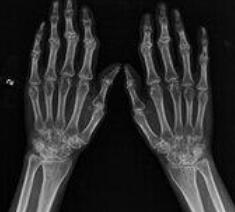

(图:张女士的手指已恶化,向内弯曲)

杜爱华主任发现张女士的类风湿仍处于不断恶化状态,加上之前一直没有进行正确地治疗,现在不及时治疗将变得非常麻烦,因此制定了详细的治疗方案。

(图: 后的张女士手指已恢复正常)